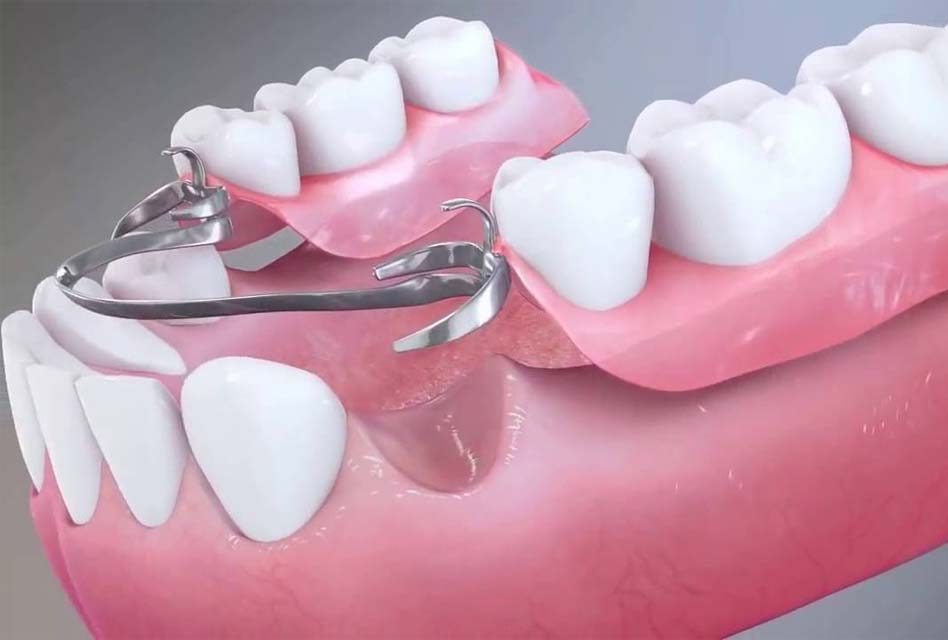

Négliger de porter une prothèse dentaire partielle peut sans doute vous paraître anodin à prime abord. Cependant, il importe de savoir que plusieurs complications risquent de survenir si vous refusez de la/les porter.